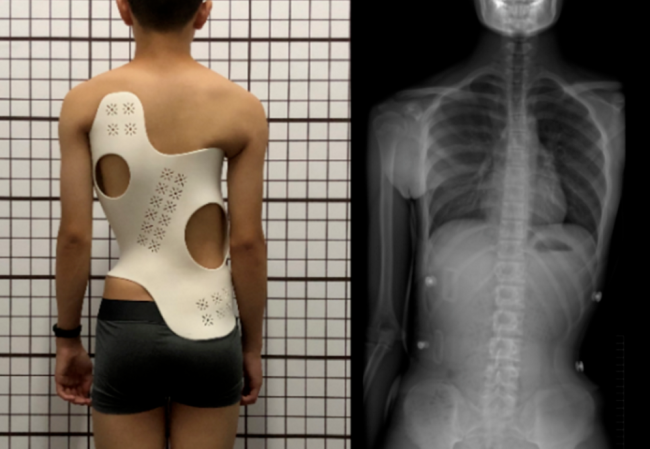

Ëæ×ſƼ¼µÄ·ÉËÙÉú³¤£¬3D´òÓ¡¼¼ÊõÔÚÒ½ÁÆÐÐÒµÖеÄÓ¦ÓÃÈÕÒæ¹ã·º£¬ÕýÔÚ³¹µ×¸Ä±ä¹Å°åµÄÒ½ÁÆÉè±¸ÖÆÔìºÍÖÎÁÆ·½·¨¡£º¼ÖÝ×ðÁú¿Ê±…